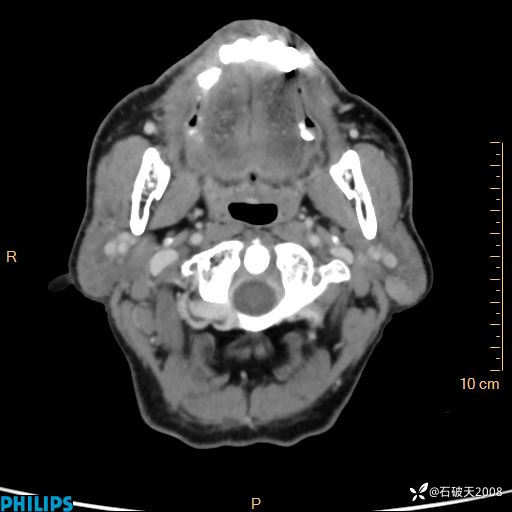

静脉期